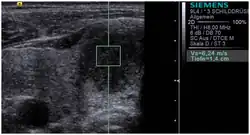

![]() Conventional ultrasonography (lower image) and elastography (supersonic shear imaging; upper image) of papillary thyroid carcinoma, a malignant cancer. The cancer (red) is much stiffer than the healthy tissue. | |

Supersonic shear imaging (SSI)

Supersonic shear imaging (SSI)[8][9] gives a quantitative, real-time two-dimensional map of tissue stiffness. SSI is based on SWEI: it uses acoustic radiation force to induce a 'push' inside the tissue of interest generating shear waves and the tissue's stiffness is computed from how fast the resulting shear wave travels through the tissue. Local tissue velocity maps are obtained with a conventional speckle tracking technique and provide a full movie of the shear wave propagation through the tissue. There are two principal innovations implemented in SSI. First, by using many near-simultaneous pushes, SSI creates a source of shear waves which is moved through the medium at a supersonic speed. Second, the generated shear wave is visualized by using ultrafast imaging technique. Using inversion algorithms, the shear elasticity of medium is mapped quantitatively from the wave propagation movie. SSI is the first ultrasonic imaging technology able to reach more than 10,000 frames per second of deep-seated organs. SSI provides a set of quantitative and in vivo parameters describing the tissue mechanical properties: Young's modulus, viscosity, anisotropy.

This approach demonstrated clinical benefit in breast, thyroid, liver, prostate, and musculoskeletal imaging. SSI is used for breast examination with a number of high-resolution linear transducers.[10] A large multi-center breast imaging study has demonstrated both reproducibility[11] and significant improvement in the classification[12] of breast lesions when shear wave elastography images are added to the interpretation of standard B-mode and Color mode ultrasound images.